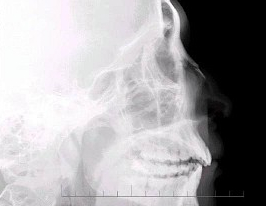

- 多项选择题 男,24岁,鼻部被击伤,如图所示,最可能的诊断是( )

A、鼻骨中段见透亮线影

B、鼻骨远端稍塌陷

C、鼻骨骨折处可见小骨片影向下方分离

D、考虑为鼻骨线性骨折

E、鼻骨粉碎性骨折

- A,B,C,E